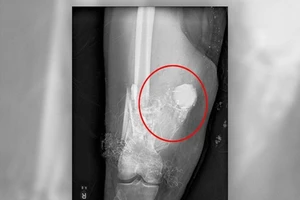

Nhờ cảnh sát lấy pháo hoa trong đùi bệnh nhân